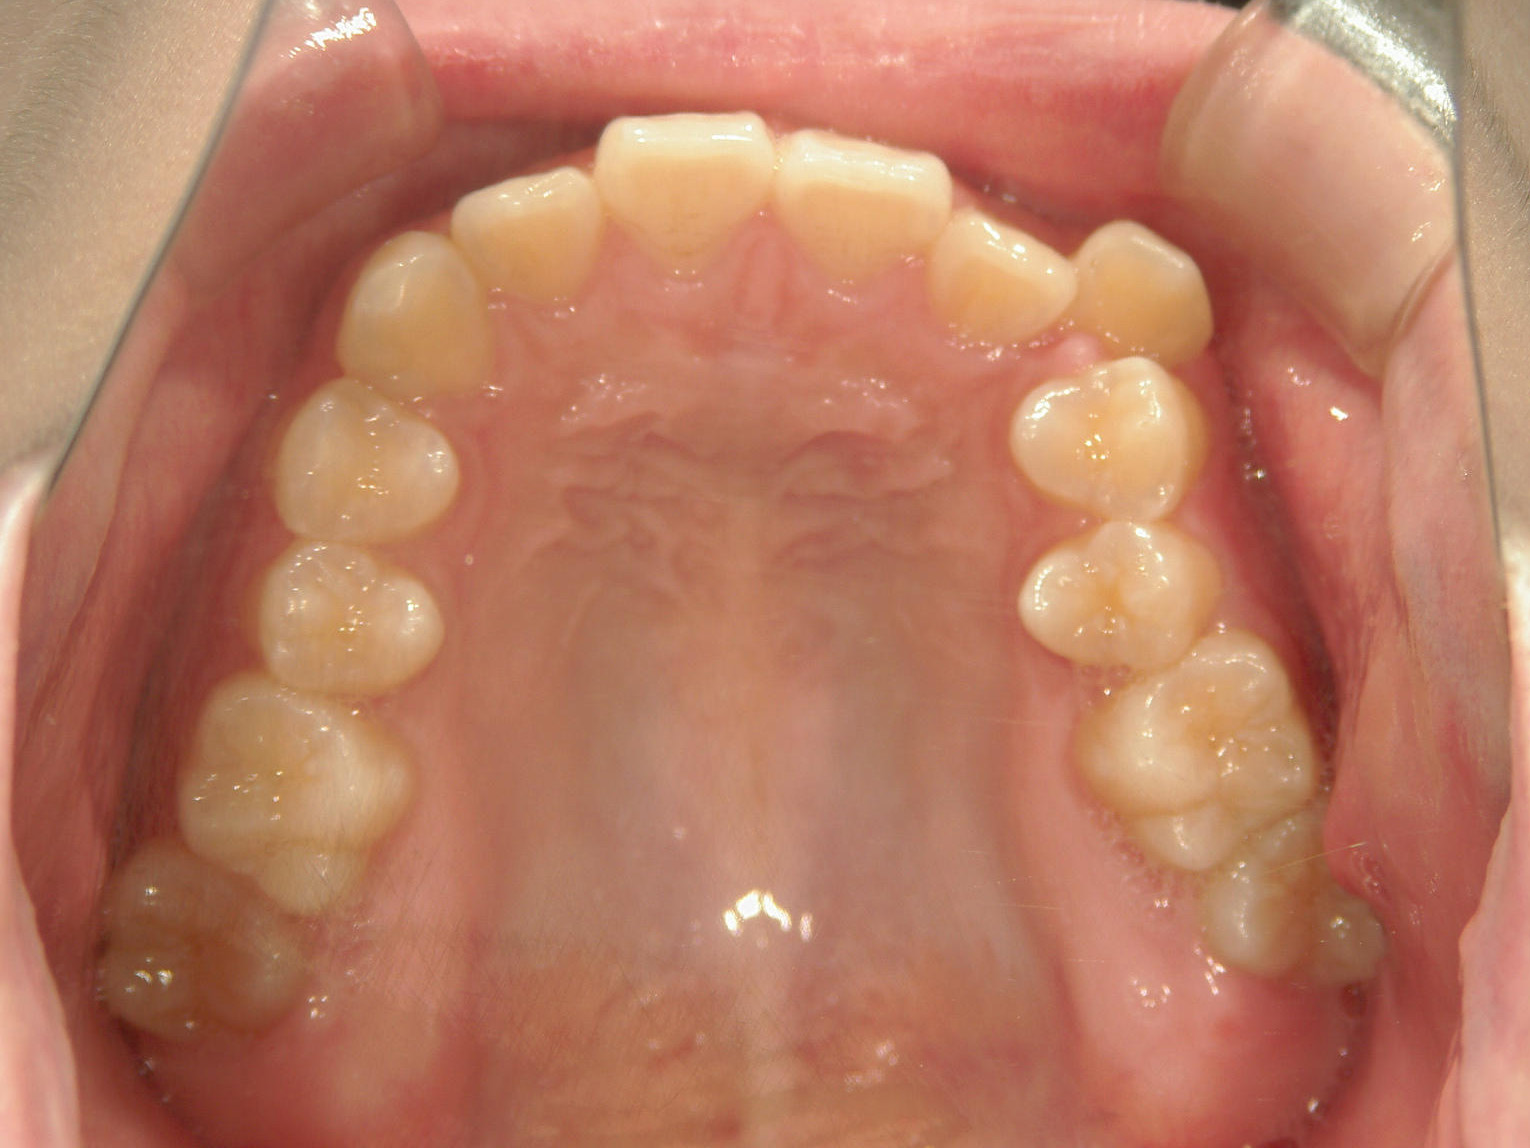

インビザライン矯正 症例(19)

主訴: 左上犬歯が出ているのが気になる

再設計3回

Ⅱ級ゴムを併用。